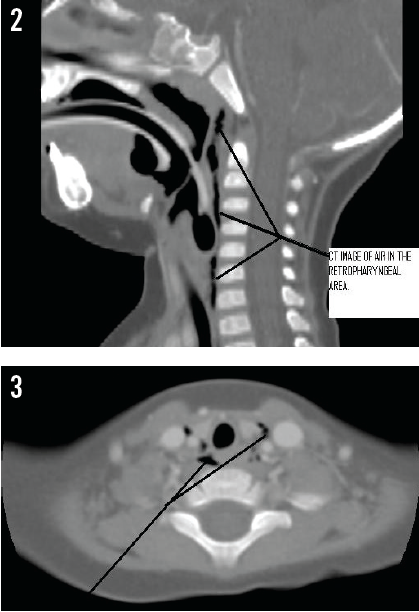

Lateral neck radiographs (Figure 1) taken at the outside hospital showed no foreign body, but the presence of a column of retropharyngeal air was concerning. Contrast computed tomography (CT) scans of the neck (Figures 2 and 3) and chest confirmed air tracking from the retropharyngeal space, through the chest, and into the mediastinum. Although the source of the air was unclear, this presentation has been seen in cases of perforation of the pharynx. Intravenous ampicillin-sulbactam was started for empiric coverage of aerobes and anaerobes to prevent mediastinitis in the context of likely perforation. Oral food and fluids were withheld.

When these findings were discussed with the parents, the mother noted that the girl had been holding an uncapped, soft-tipped marker when she had begun coughing and crying before admission. This suggested that the free air likely had resulted from self-inflicted injury with the marker to the oropharynx.